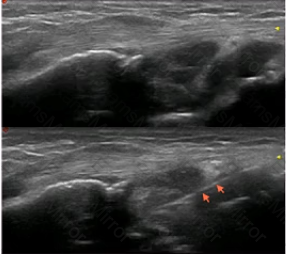

The image below shows the injection of the dorsal wrist region in a patient with rheumatoid arthritis. The needle is indicated by the arrows. Considering the ultrasound findings, which of the following is MOST appropriate in completing the injection?